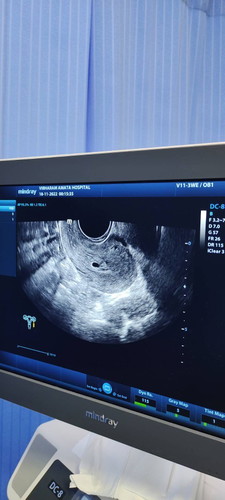

กลัวท้องลมมากเลยค่ะ6วิก5วันไม่เห็นตัวน้องเลยก่อนไปตรวจมีมูกเลือกออกด้วยนะค่ะจะเป็นอะไรไหมหมอนัดอีกที1ธันวาคม

น้องอาจจะยังเล็กอยู่ค่ะแม่ รอน้องอีกหน่อยค่ะ